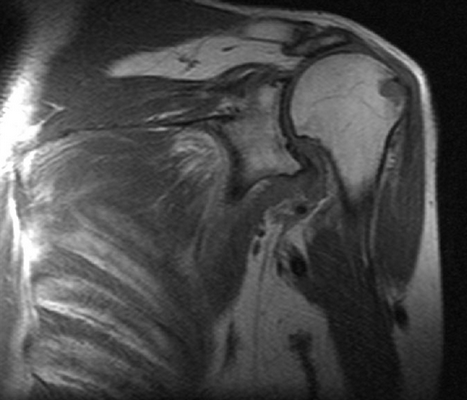

На серии МР-томограмм, взвешенных по Т1 и Т2, а также протонной плотности с использованием режима жироподавления в аксиальной, косой корональной и косой сагиттальной плоскостях определяются структуры правого плечевого сустава. Соотношение в суставе на момент исследования не нарушено. Субакромиальное пространство составляет 6 мм (сужено). Суставная впадина лопатки уплощена, контуры ее ровные, с признаками субкортикального остеосклероза. По краям суставной впадины лопатки имеются небольшие остеофиты. Головка плечевой кости округлой формы не деформирована. Суставной хрящ неоднородной структуры, неравномерно истончен, целостность его не нарушена.

Суставная губа на всем протяжении прослеживается, дегенеративно изменена, без отчетливых признаков нарушения целостности. Средняя суставно-плечевая связка неравномерно утолщена, без нарушения целости, но вокруг отмечается небольшое количество выпота. Сухожилие надостной мышцы на протяжении 24 мм (преимущественно в области мышечного брюшка) утолщено, разволокнено с признаками отека и участками обызвествления, преимущественно изменения отмечаются в передней порции волокон - повреждение сухожилия дегенеративного генеза. Вокруг мышечного брюшка надостной мышцы отмечается небольшой отек межмышечной клетчатки.

Сухожилие подлопаточной мышцы в области прикрепления к малому бугорку плечевой кости утолщено, минимально разволокнено, общая целость его и натяжение сохранены (изменения по типу тендиноза). Сухожилия подостной мышцы в области прикрепления к плечевой кости имеют неоднородную МР- структуру, за счет дегенеративных изменений, целость не нарушена. Сухожилия малой круглой мышцы не изменено. Визуализируется умеренное скопление свободной жидкости в полости плечевого сустава, умеренное в подклювовидной сумке. Сухожилия длинной головки двуглавой мышцы плеча не изменено, вдоль него минимальное количество выпота. Правый акромиально-ключичный сустав дегенеративно изменен: суставные поверхности имеют неровные контуры с наличием краевых костных разрастаний, сами суставные концы с субкортикальным остеосклерозом. Капсула сустава умеренно утолщена.

ЗАКЛЮЧЕНИЕ: МР-картина остеоартроза правого плечевого и акромиально-ключичного сустава I-II ст., признаков импинджмент синдрома с частичным повреждением сухожилия надостной мышцы, умеренно выраженные дегенеративные изменения сухожилия подлопаточной мышцы по типу тендиноза. Синовит. Умеренный теносиновит.